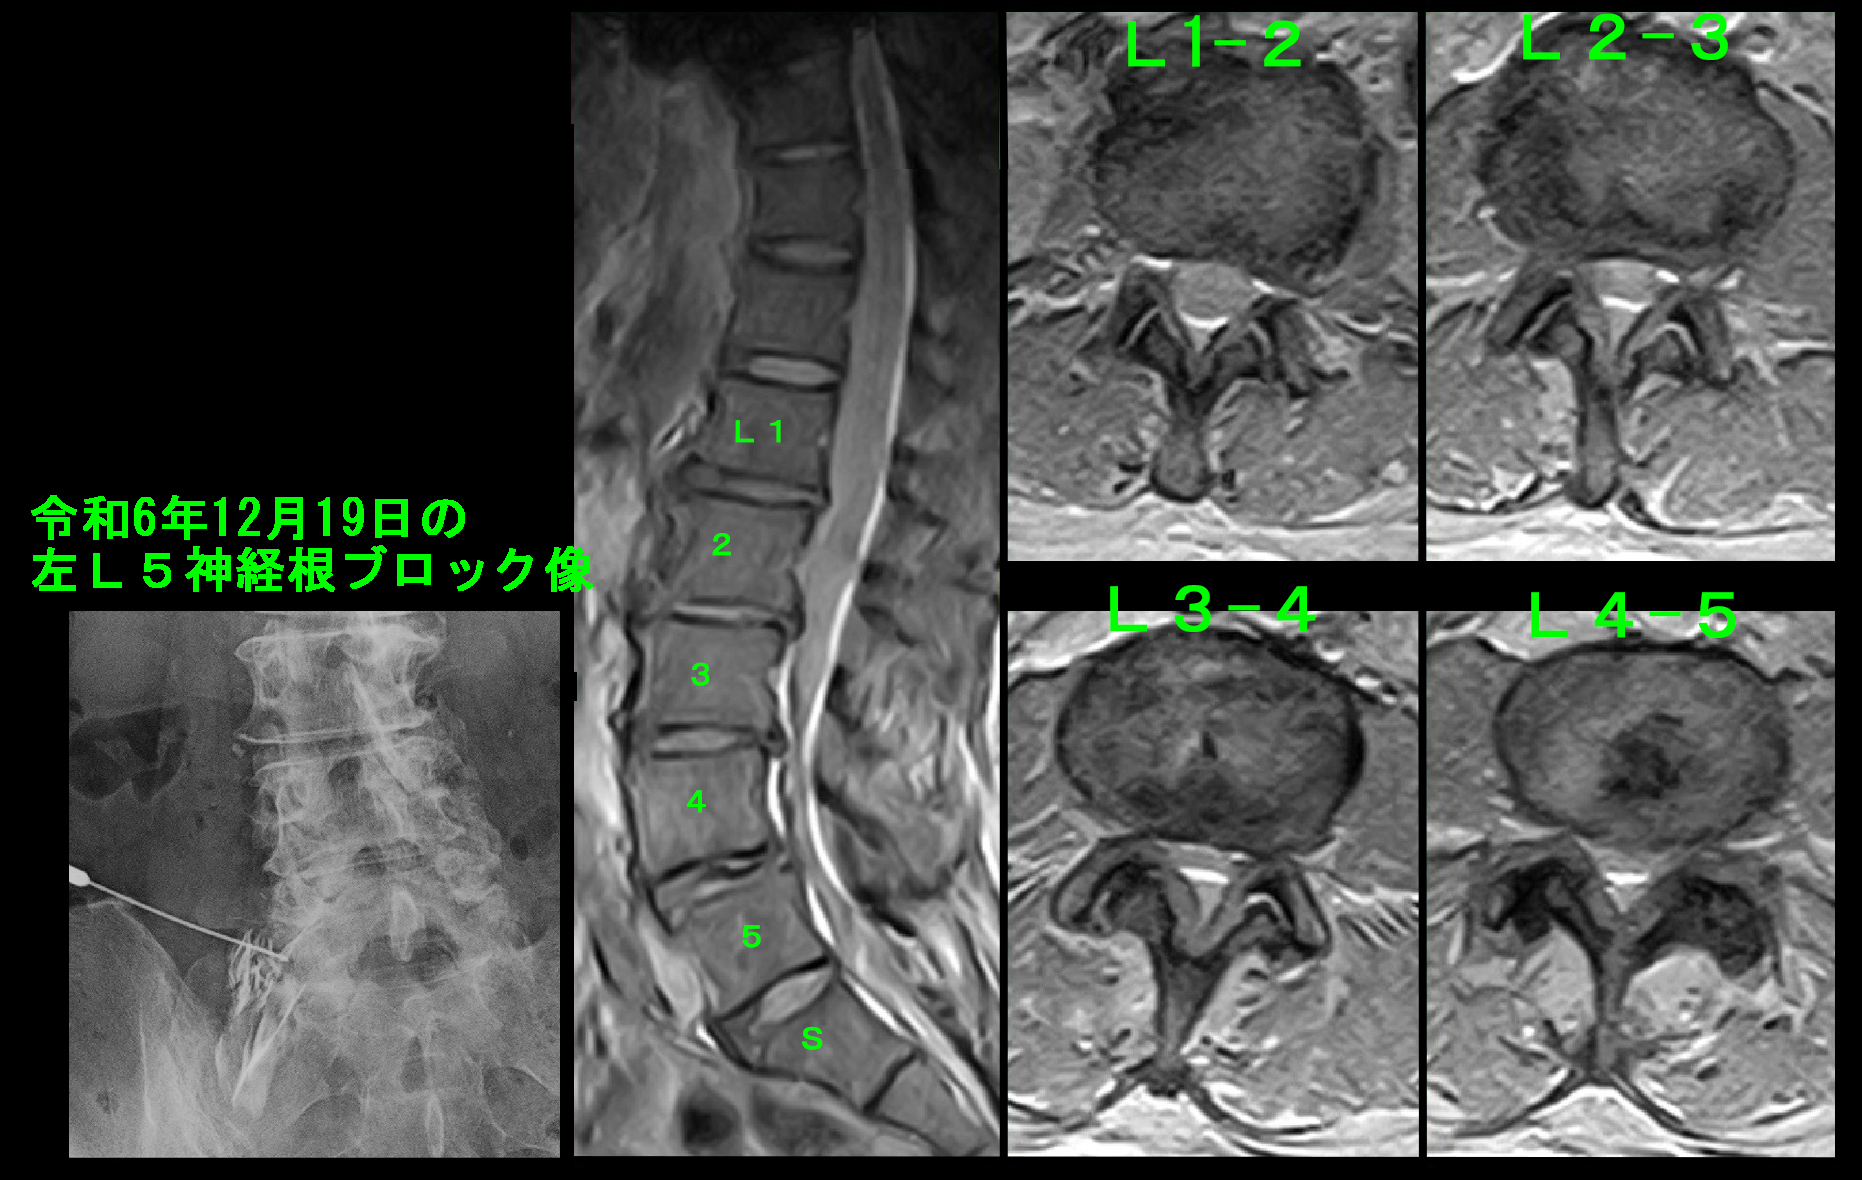

64才女性。令和6年12月19日腰痛と左ふくらはぎの痛みで寝返りが困難、夜も十分眠れないということで受診された患者さんです。腰椎MRI検査を行い、重度の脊柱管狭窄(腰椎部の老化により脊髄が圧迫されて腰痛・下肢痛=坐骨神経痛が発症する状態です)を認めたL45高位で神経根ブロックを行い、症状の軽減がえられました。

65才女 MR.jpg10か月後の7年10月30日に左臀部痛で再診され、ブロックを希望で受診されました。10月15日、日帰りで東京に車で出かけ(本人は後部座席に座っていて、1時間ごとに休憩をとっていたそうです)、腰痛が再発し、10月29日に畑仕事を30分ほどしたら右臀部痛が悪化したため、10か月前と同じと判断しブロックを希望されて受診されました。